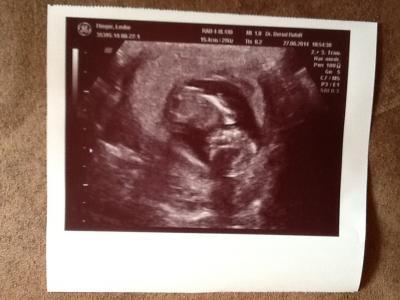

Endlich war es gestern soweit. Und es ging alles so schnell. Kaum war ich da musste ich erstmal eine Urinprobe abgeben dann Blutdruck und Blutzuckermessen. Dann wurde es spannend. Die Arzthelferin wollte mich "abhören". Wusste garnicht was jetzt kommt. Und damit meinte sie meinen Bauch^^ es war so unglaublich als man das Herz schlagen hören konnte. Sie meinte es hat eine Frequenz von 124 und das ist total normal.Dann kam ENDLICH der Ultraschall. Es war so schön. Seit meinem letzten Termin vor 4 Wochen ist das Baby von einer Qualle zu einem richtigen Menschen geworden. Es hat sogar richtig rum gezappelt

Es hat eine SSL von 6,6. Und mein ET hat sich geändert auf den 03.01.2015

Anbei noch ein Foto von meinem süßen Melonenkopf